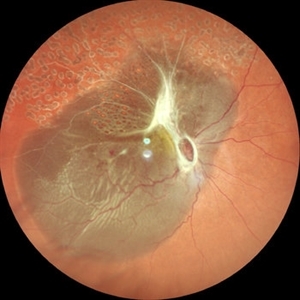

Subretinal Hemorrhage

A 79 Year old male on anticoagulants with massive subretinal hemorrhage secondary to polypoidal choroidal vasculopathy (PCV)

Photographer: SHISHIR VERGHESE, AMITA EYE CARE

Condition/keywords: polypoidal choroidal vasculopathy (PCV), subretinal hemorrhage